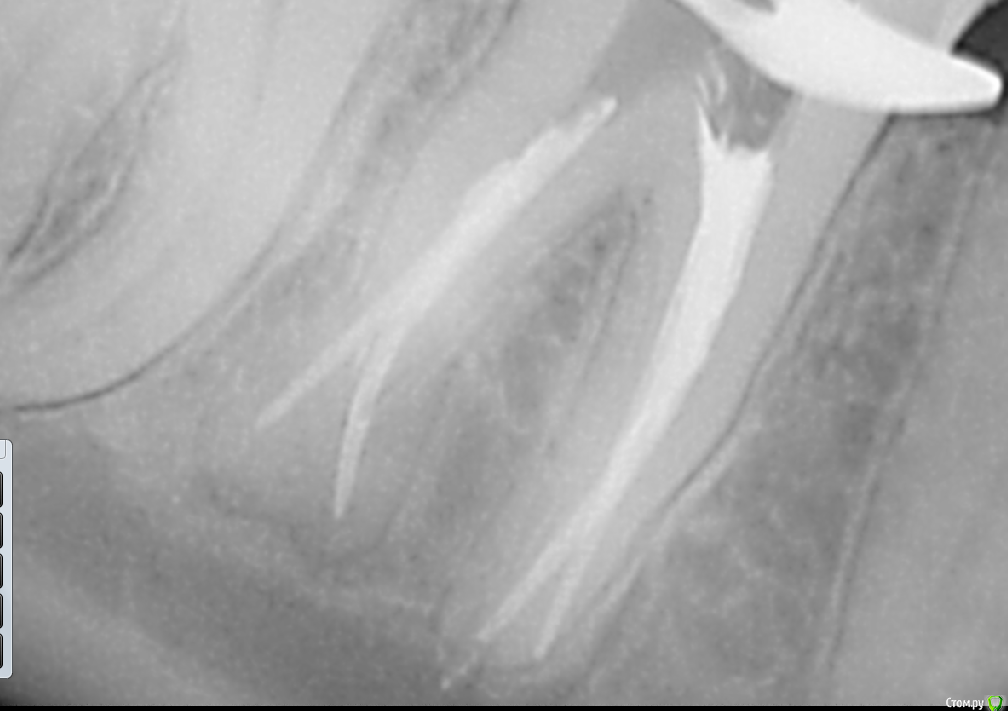

dr.Dre Опубликовано 16 апреля, 2016 Поделиться Опубликовано 16 апреля, 2016 Добрый день коллеги,пациентка 17 лет 26 зуб,с проходимых каналов только небный,жалобы на ноющую боль.Как поступить в данной ситуации? Ссылка на комментарий

Гарриевич Опубликовано 16 апреля, 2016 Поделиться Опубликовано 16 апреля, 2016 Устья не там ищете. Надо мезиальнее искать медиальнее искать мезиальные. С дистальным такая же тема, ушли дистально. Если у вас такая ситуация что не видно устьев, то отмачивайте все в хлорке, долго и лучше гелем с активацией 2 Ссылка на комментарий

skeettrap Опубликовано 16 апреля, 2016 Поделиться Опубликовано 16 апреля, 2016 (изменено) Не используйте вращающие инструменты в области дна пульповой камеры. Создали доступ и отложите в сторону. Лучше УЗ насадки - Р1 например. Изменено 16 апреля, 2016 пользователем skeettrap 2 Ссылка на комментарий

dr.Dre Опубликовано 16 апреля, 2016 Автор Поделиться Опубликовано 16 апреля, 2016 Не используйте вращающие инструменты в области дна пульповой камеры. Создали доступ и отложите в сторону. Лучше УЗ насадки - Р1 например.Доступ делал ультразвуком Ссылка на комментарий

vse32 Опубликовано 19 мая, 2016 Поделиться Опубликовано 19 мая, 2016 Присоединюсь ко всем вышеперечисленным советам.Но попрошу всех, у кого бывают проблемы с поиском каналов, вспомнить одно золотое правило.В канал, зачастую, можно зайти только под вполне конкретным углом. Отклонение - неудача. Устье есть, инструмент не лезет. Играйтесь с направлением инструмента.На снимке зуб как раз достойный моих нравоучений. Ссылка на комментарий